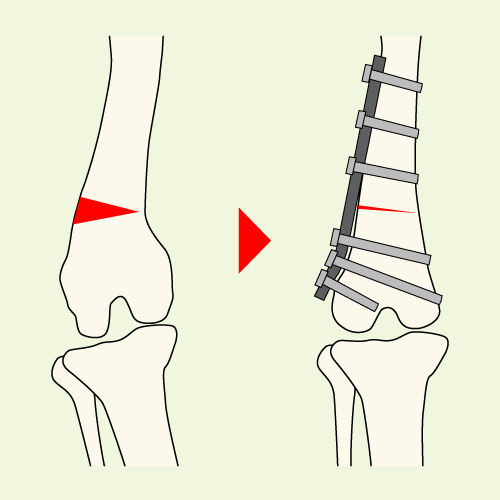

DFO(大腿骨遠位骨切り術)

主にグレード4の重症例で適応される術式で、大腿骨の湾曲変形を骨切によって矯正します。湾曲変形を認める骨の一部を楔形に抜きだして、再び接合する事で湾曲矯正を行う術式です。